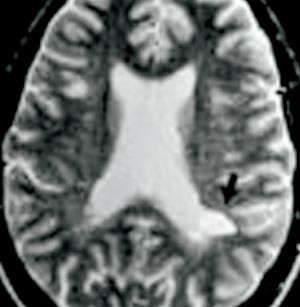

Multippel sklerose er en demyeliniserende sykdom med et uforutsigbart og svært varierende forløp. Hos de fleste debuterer sykdommen med et såkalt klinisk isolert syndrom. Bare om lag en tredel av disse får innen ett år et nytt utbrudd og dermed en sikker diagnose. Hos mange tar det flere år før diagnosen er fastslått.

Blant 103 pasienter med nyoppståtte symptomer og MR- og cerebrospinalvæskefunn som støttet diagnosen multippel sklerose, hadde 22 antistoffer i blod mot myelinproteinene MOG og MBP; 42 hadde antistoffer mot bare MOG-protein (1). I de påfølgende fire år (median) utviklet henholdsvis 21 (95 %) og 35 (83 %) av disse et nytt utbrudd som medførte sikker MS-diagnose, mot bare ni av de 39 seronegative pasientene (23 %; p < 0,001).